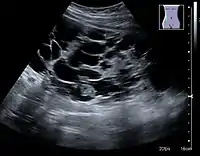

Category IIF

A Bosniak category IIF cyst. This one is 3 cm wide, with calcifications within its wall, seen as very radiodense (white in this presentation) areas in its margins. There is also a septation which is calcified. Yet, the cyst does not show enhancement (uptake of contrast).

This category includes renal cysts with multiple thin septa, a septum thicker than hairline, slightly thick wall, or with calcification, which may be thick. It also includes intrarenal cysts larger than 3 centimetres (1.2 inches) if:

• there is no contrast enhancement (otherwise category III).[7]

• there is high attenuation or there is a maximum 25% of their walls visible outside the kidney (otherwise category II).[3]

Category IIF cysts have a 5–10% risk of being kidney cancer, and therefore follow-up is recommended. However, there is no consensus recommendation on the appropriate interval of follow up.[7]